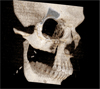

This 22-year-old patient underwent a posterior right maxillary resection extended to the orbital floor (Brown III-b class) due to a malignant peripheral nerve sheath tumor (MPNST). Teeth 14 to 17 were sacrificed during surgery (Figs. 2 and 3). Primary reconstruction was performed using a free radial forearm flap, thereby avoiding the need for a vascularized bone graft. Two ZI were placed in positions 14 and 17, along with a CI in position 15, following ramus bone grafting (Fig. 4). The resulting tripod configuration allowed for the stable fixation of the prosthesis and immediate functional loading. At four years of follow-up, both ZI and CI show a 100% survival rate, with a fully functional prosthesis and an uneventful postoperative course.

Fig. 2 Three-dimensional reconstruction showing the post-surgical defect classified as a Brown III-b class. |